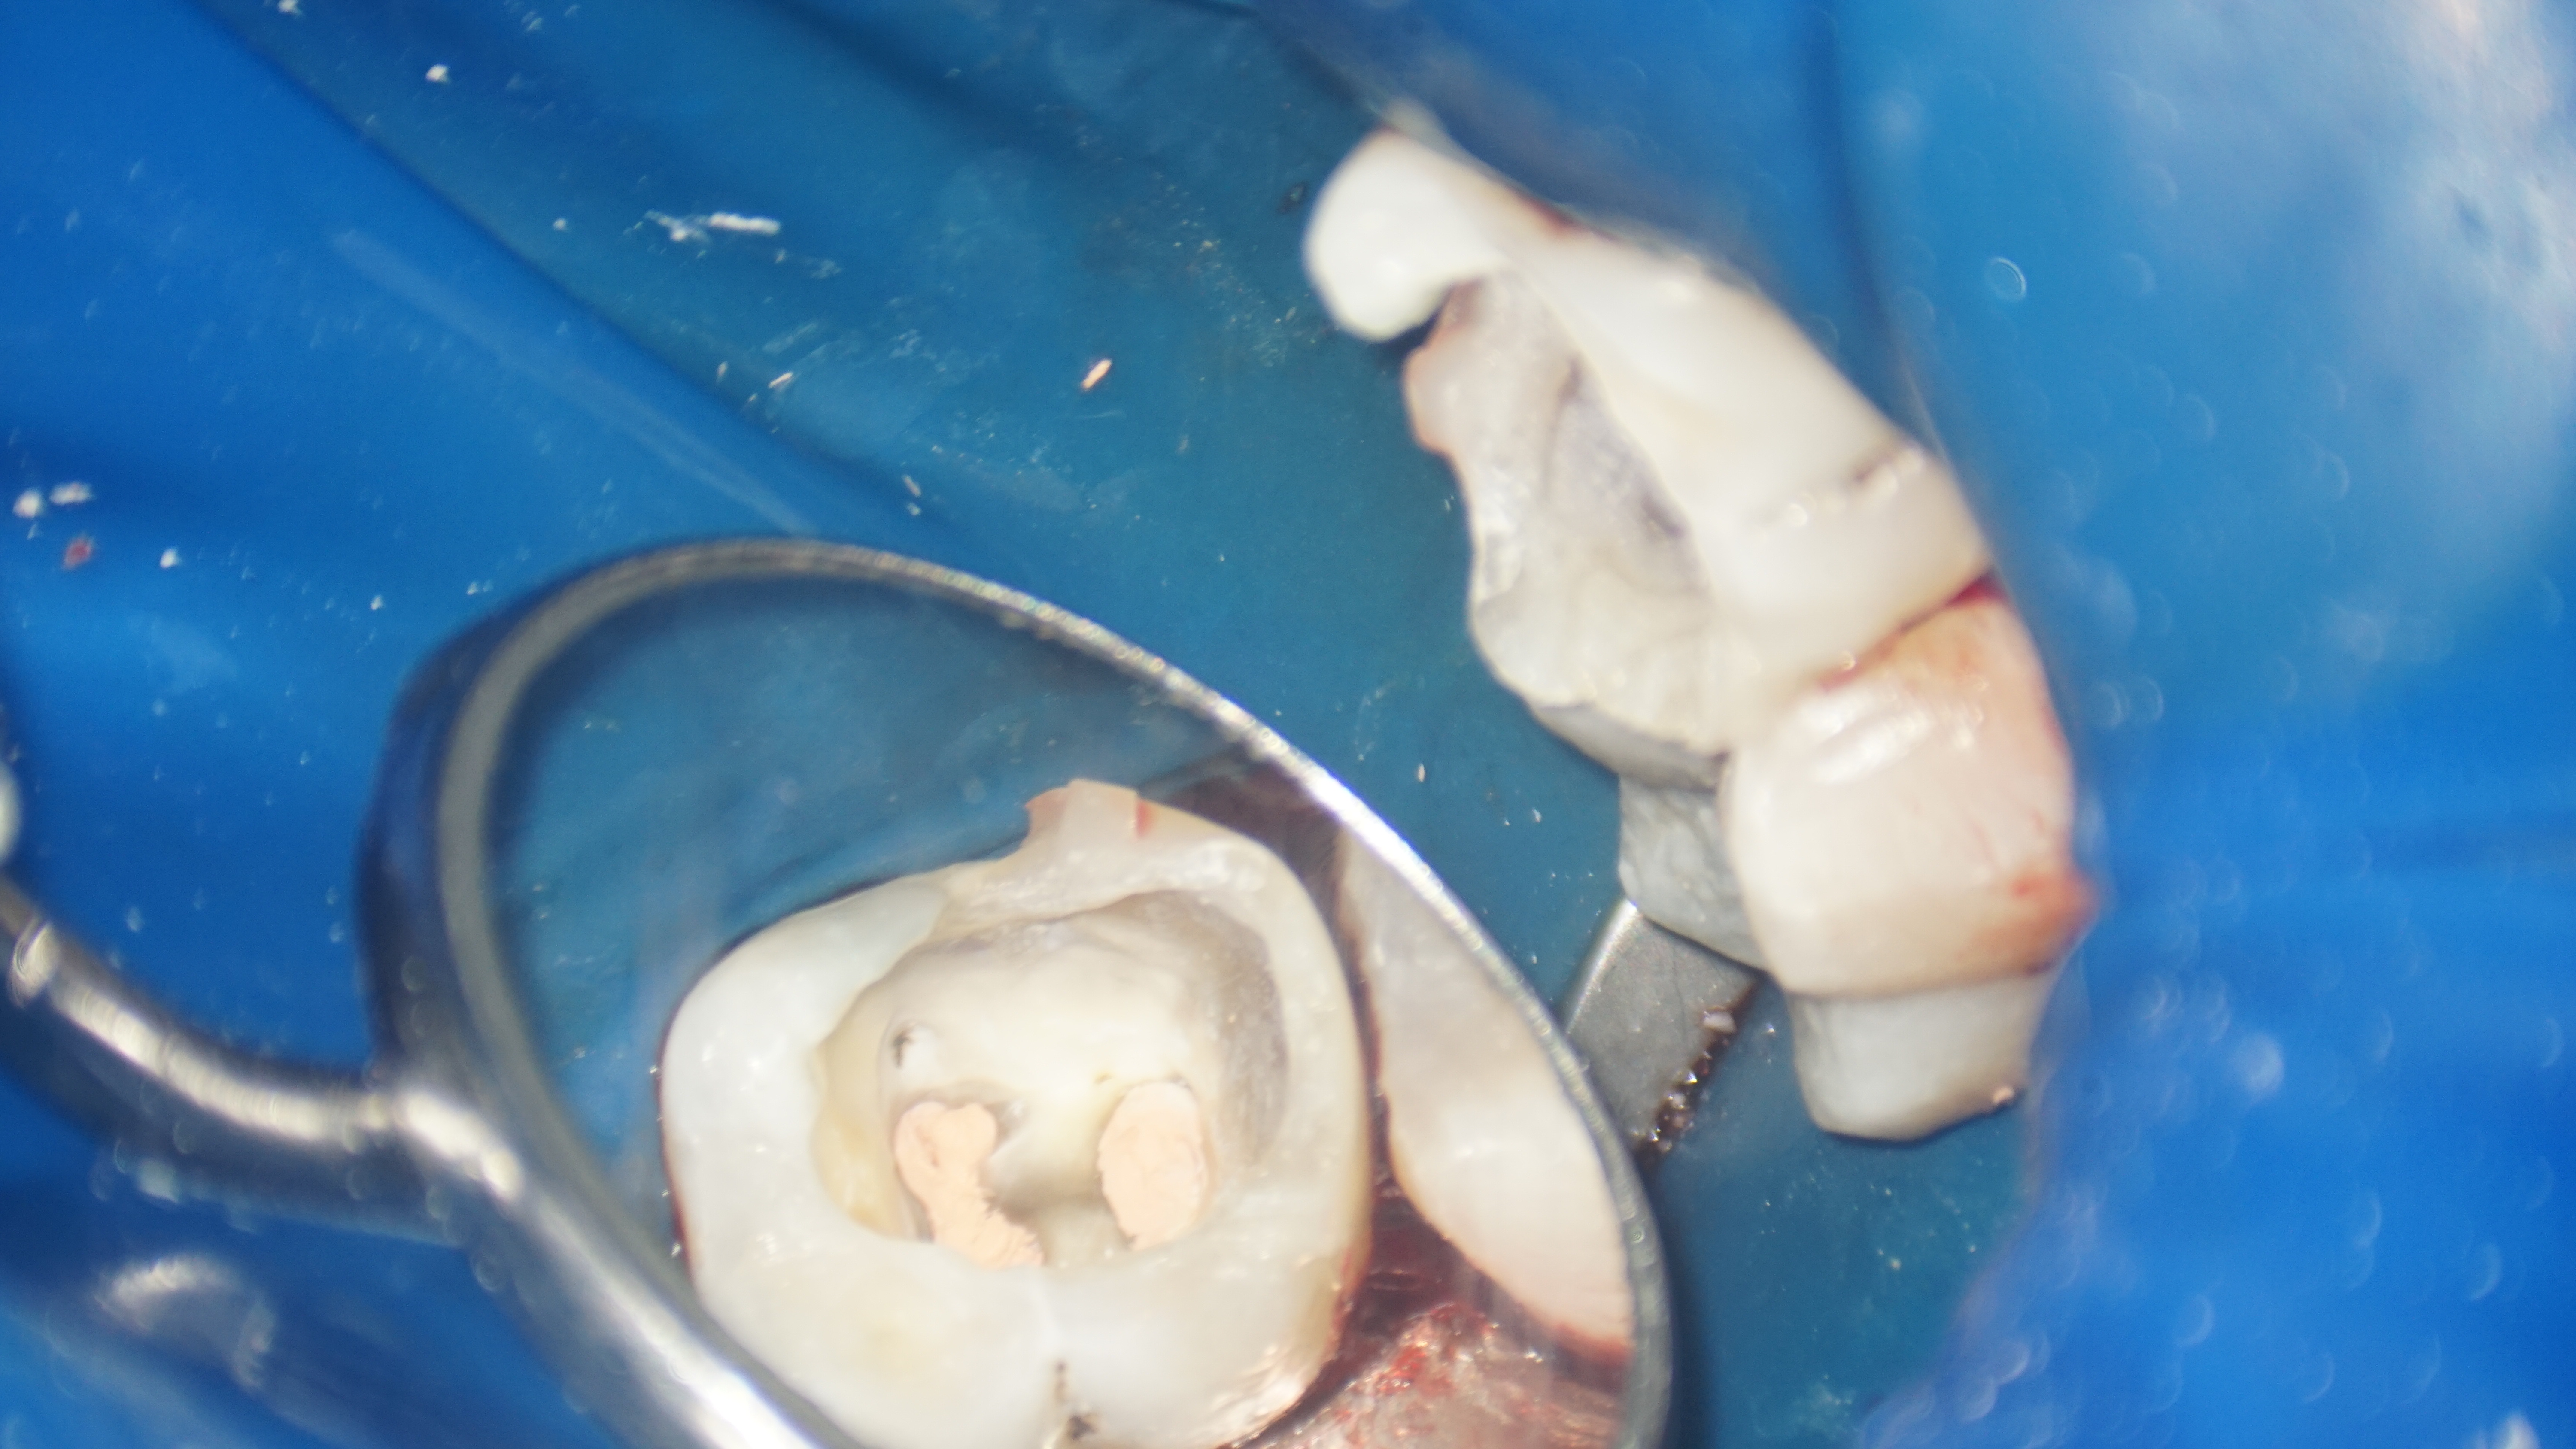

Cazul descris este al unui pacient care s-a prezentat la noi in clinică cu plângeri referitoare la dintele 46. Acest dinte a fost tratat anterior, în urma intervenţiei a rămas câte un fragment de ac în fiecare radacina.

Pacientul prezenta simptome de parodontită apicală, manifestate prin dureri și disconfort la masticatie. Parodontita apicală cronică reprezintă o inflamație persistentă la nivelul țesuturilor de la vârful rădăcinii dintelui, rezultată din infecția bacteriană al canalului radicular. După evaluarea clinică și radiografică, s-a constatat că fragmentele de ac separate accidental împiedicau vindecarea completă a infecției și a inflamației. Tratamentul endodontic inițial nu a fost suficient pentru a remedia problema.

Astfel, s-a decis refacerea tratamentului iniţial, fapt ce a implicat instrumentarea canalelor radiculare și curățarea lor adecvată, realizând bypass-ul (ocolirea) fragmentului din rădăcina mezială şi înlăturarea celui din rădăcina distală. După finalizarea procedurilor, pacientul a raportat dispariția simptomatologiei și ameliorarea disconfortului la masticatie.